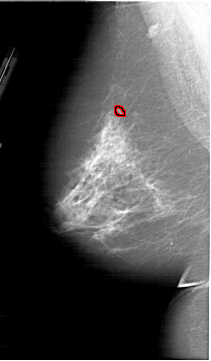

A_1913_1.LEFT_MLO

FILE: A_1913_1.LEFT_MLO.OVERLAY

TOTAL_ABNORMALITIES 1

ABNORMALITY 1

LESION_TYPE CALCIFICATION TYPE PLEOMORPHIC DISTRIBUTION CLUSTERED

ASSESSMENT 4

SUBTLETY 4

PATHOLOGY BENIGN

TOTAL_OUTLINES 1

BOUNDARY